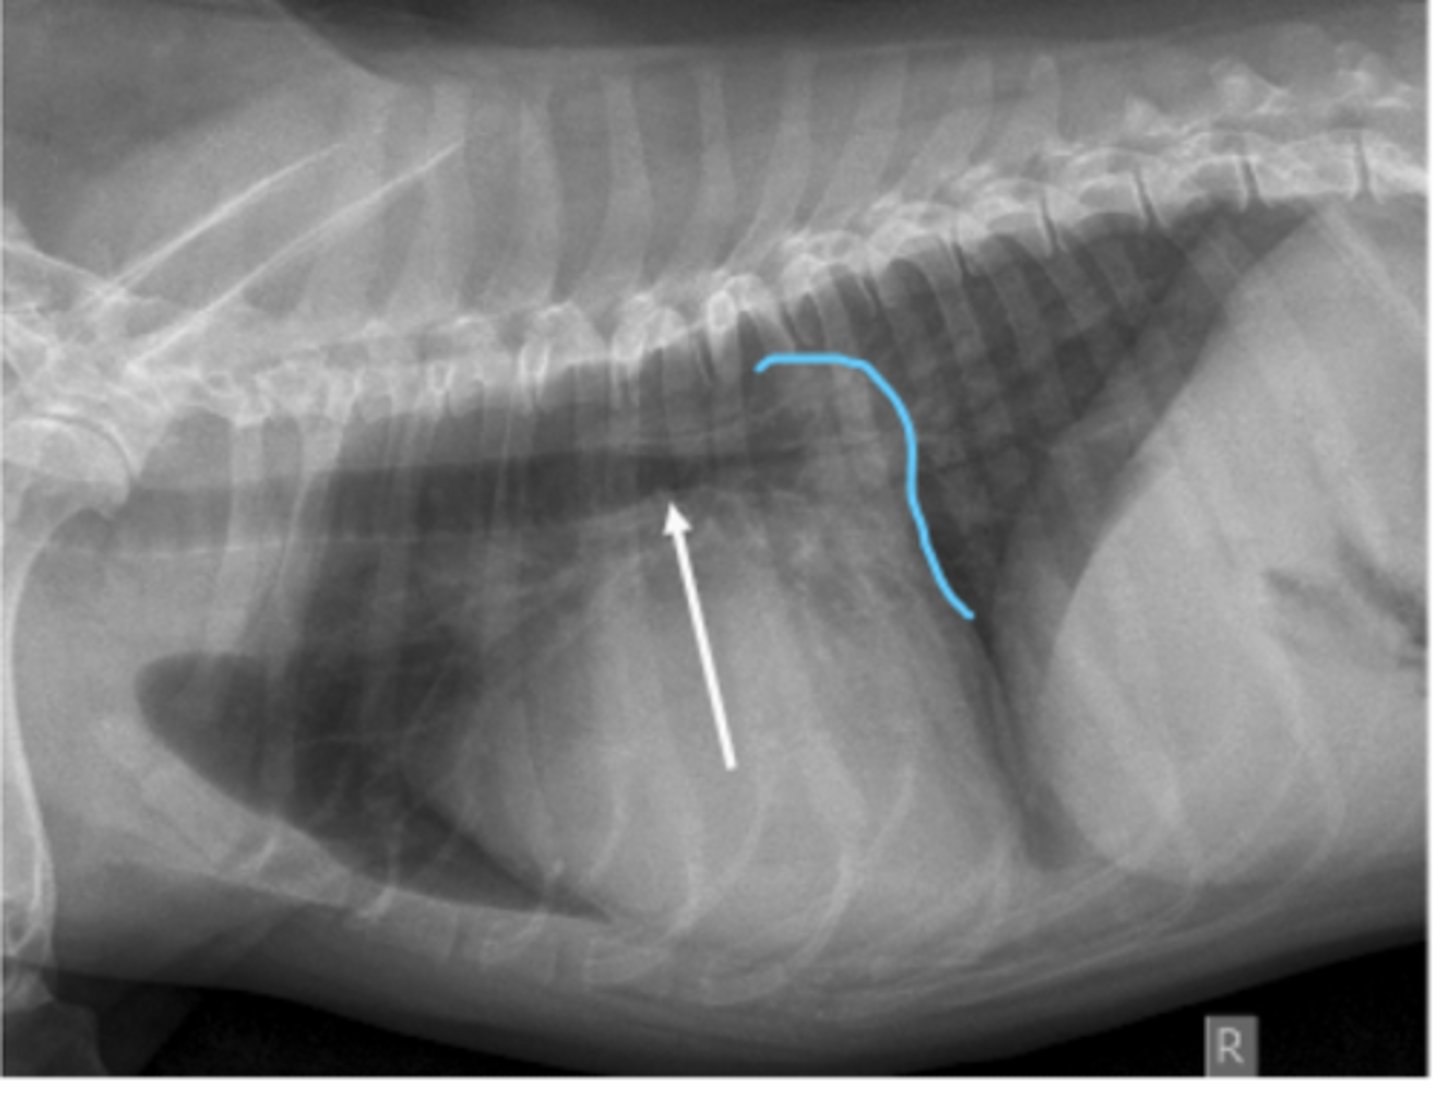

torsión esplénica

(C invertida)

patología: